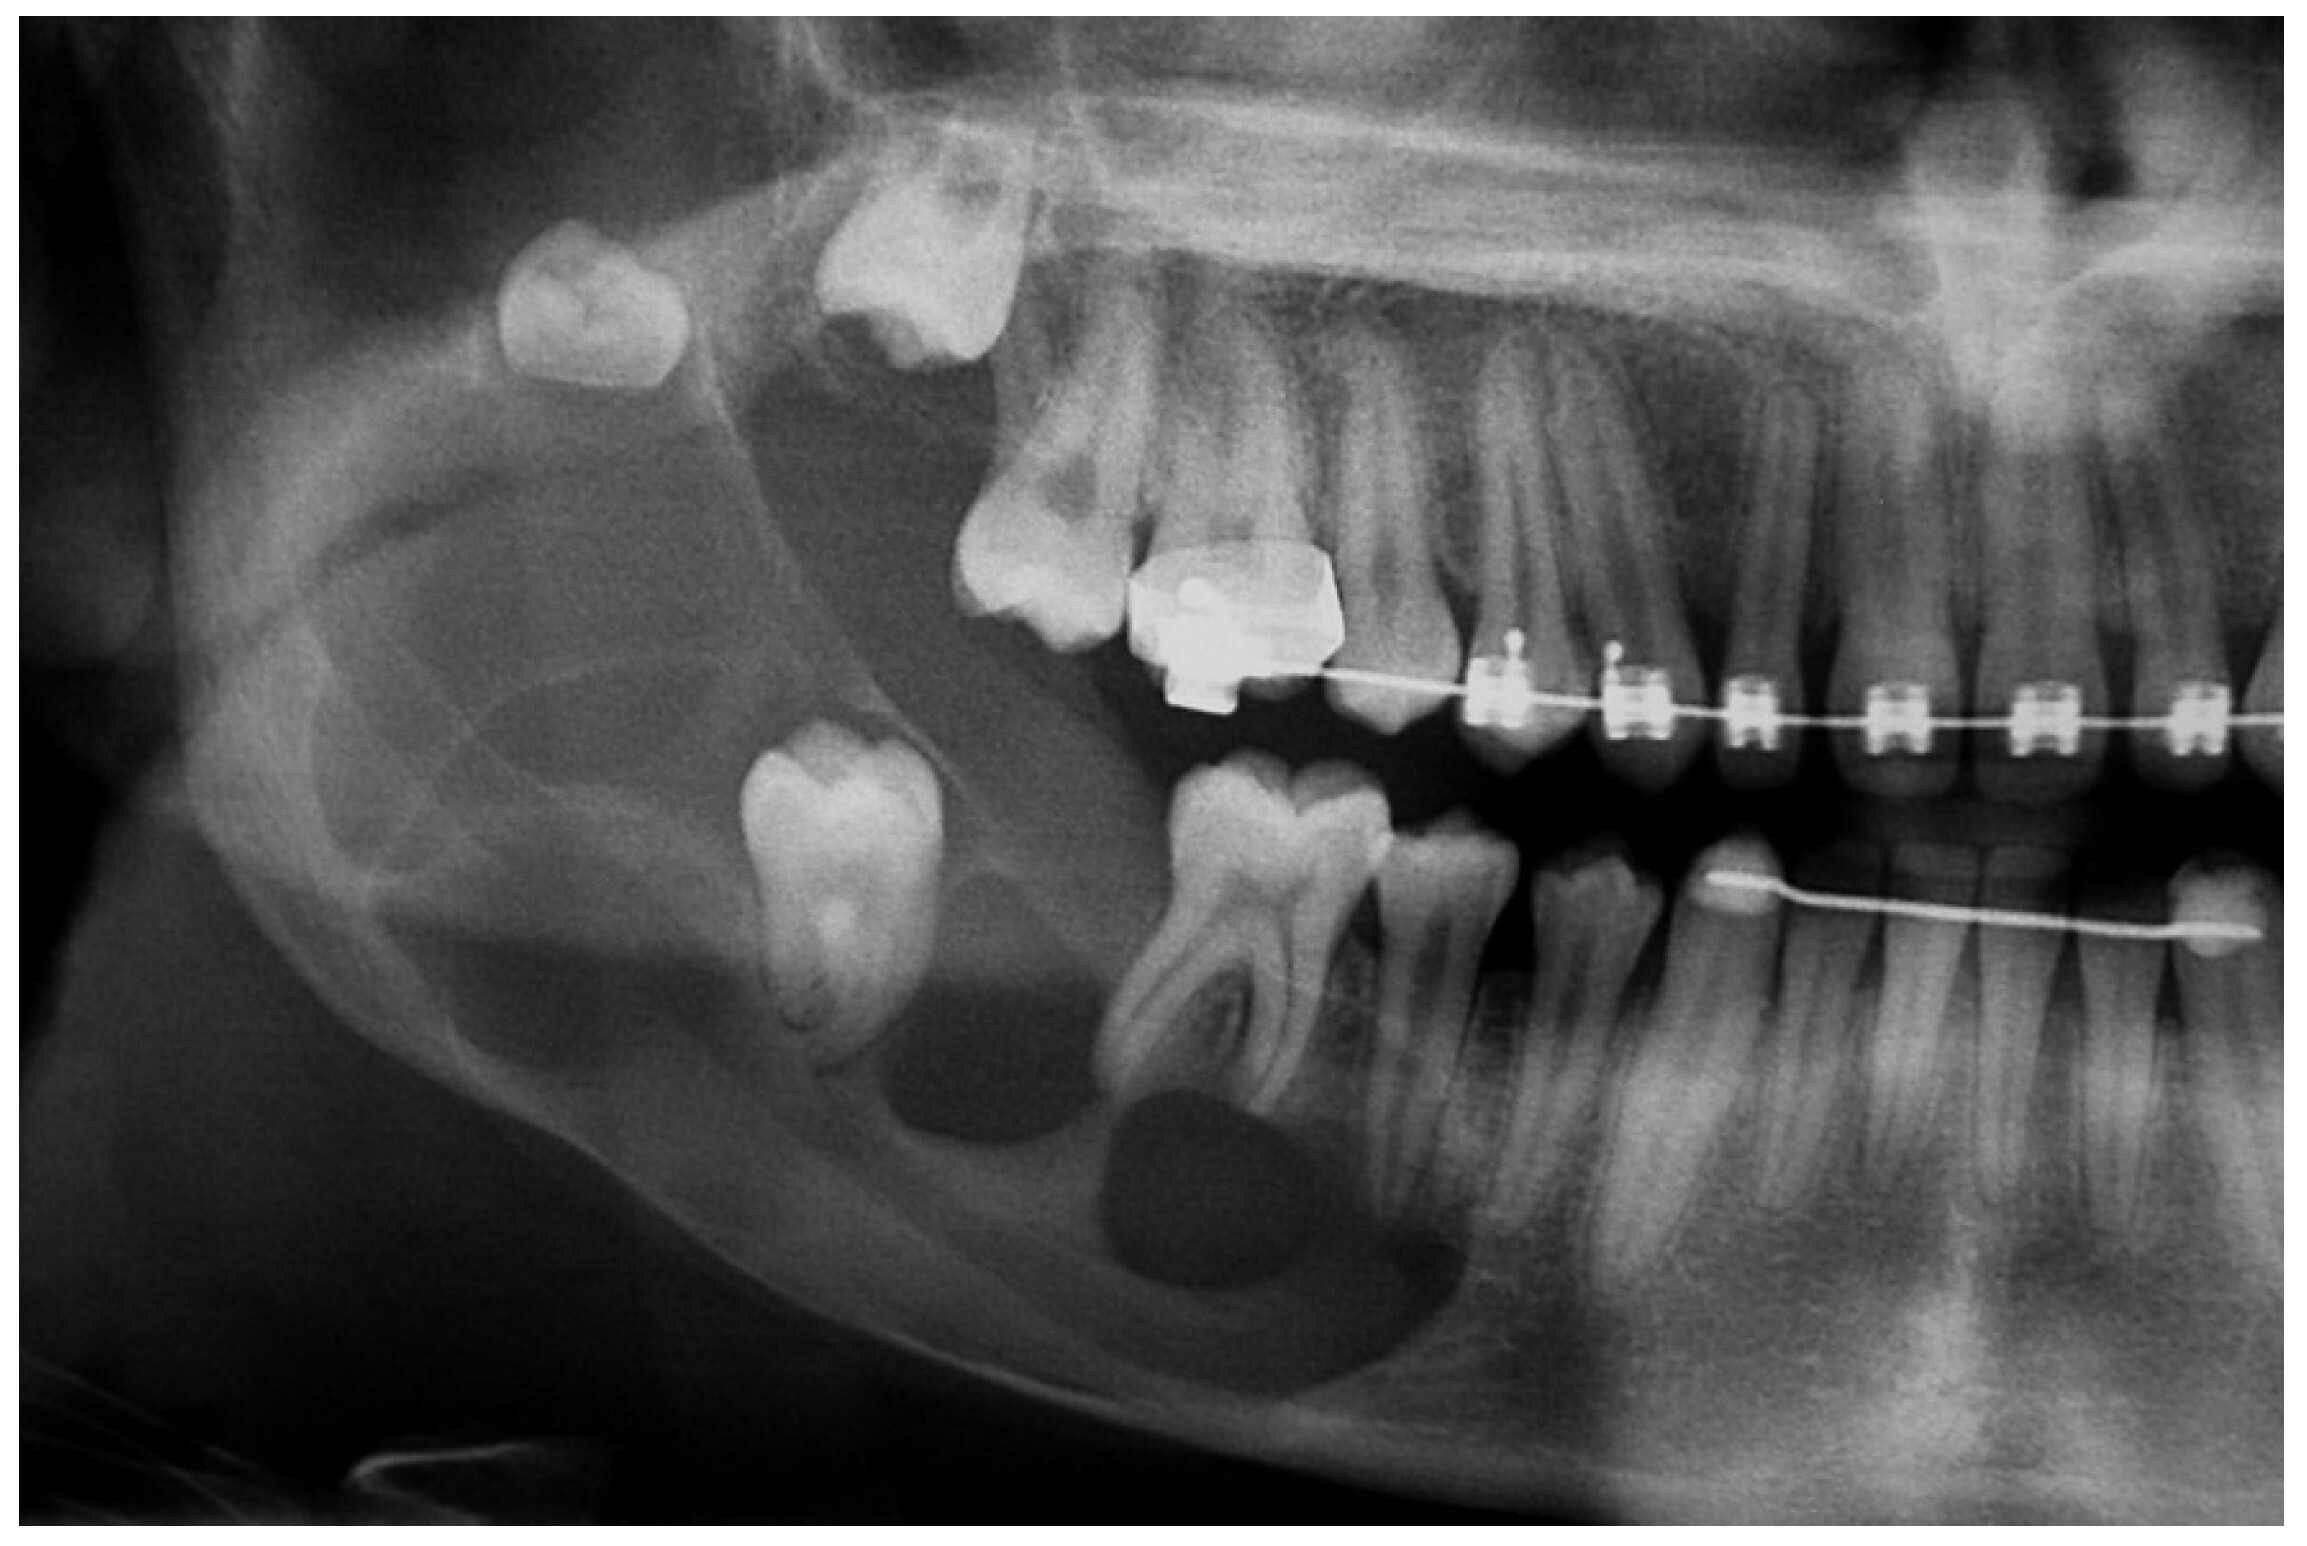

Because these cysts grow slowly and are often near the back of your mouth, you probably wouldn't even know one is there until your dentist tells you about it. They could see it in a routine examination. If your dental professional is checking on your wisdom teeth coming in, they may use a radiograph (x-ray) and discover it, or an orthodontist may notice a dentigerous cyst during a consultation for braces or clear aligners.

Your general dentist may be able to remove your cyst if they have special surgical training, but you'll likely be referred to an oral surgeon. Oral surgeons frequently encounter many types of cysts while removing wisdom teeth.

First, you'll receive a local anesthetic. Then your oral surgeon will likely remove the tooth and the cyst. If your cyst is small, your dental professional may be able to drain the cyst or remove the cyst by itself. For larger, more severe cysts, your surgeon may perform a bone graft if you've experienced bone loss.